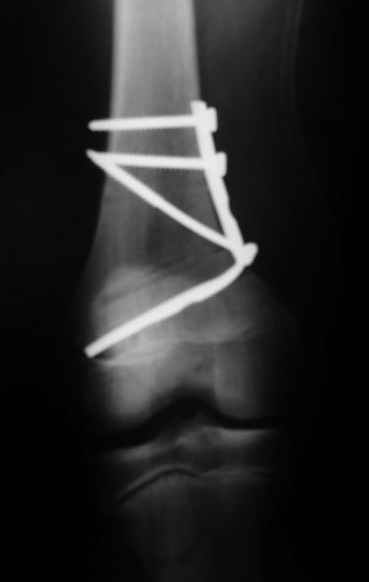

Как вариант решения прогрессирующей вальгусной деформации коленного сустава я бы предложил косую остеотомию дистального отдела бедра с фиксацией пластиной и компрессирующим винтом.

Взгляните на снимки , может быть это вам поможет.

Около 5 лет применяю этот тип дистальной остеотомии бедра для коррекции механической оси Н/К ( более 20 случаев) - достаточно эффективная операция.

- Конечно, другая: я применял этот тип остеотомии при различных состояниях, приводящих к деформации механической оси сустава, но техника её тандартна,

расчеты индивидуальные.

-Деформация оси сустава может быть варусной или вальгусной, причины - структурные изменения в латеральном -или медиальном отделе сустава (переломы, патология зон роста, дисплазии, дегенеративные процессы) результат лечения внутри- или внесуставного перелома и восстановление оси обуславливается анатомичностью репозиции и адекватностью фиксации. Нередко в запущенных -неправильно срасшихся unicompartmental внутрисуставных переломах восстановление оси и опороспособности достигается периартикулярными

остеотомиями...